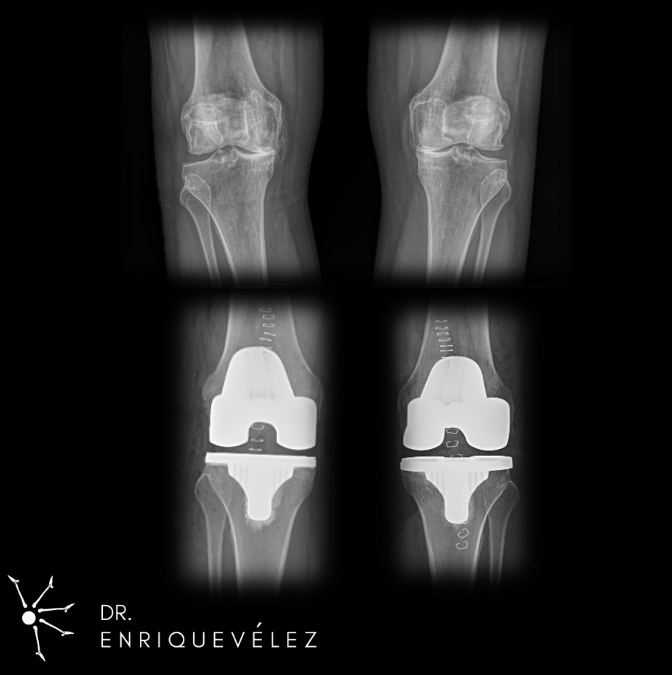

KNEE REPLACEMENT SURGERY

Knee replacement is usually recommended when chronic pain, stiffness, or reduced mobility caused by arthritis or injury can no longer be managed with medication, physical therapy, or other non-surgical treatments.